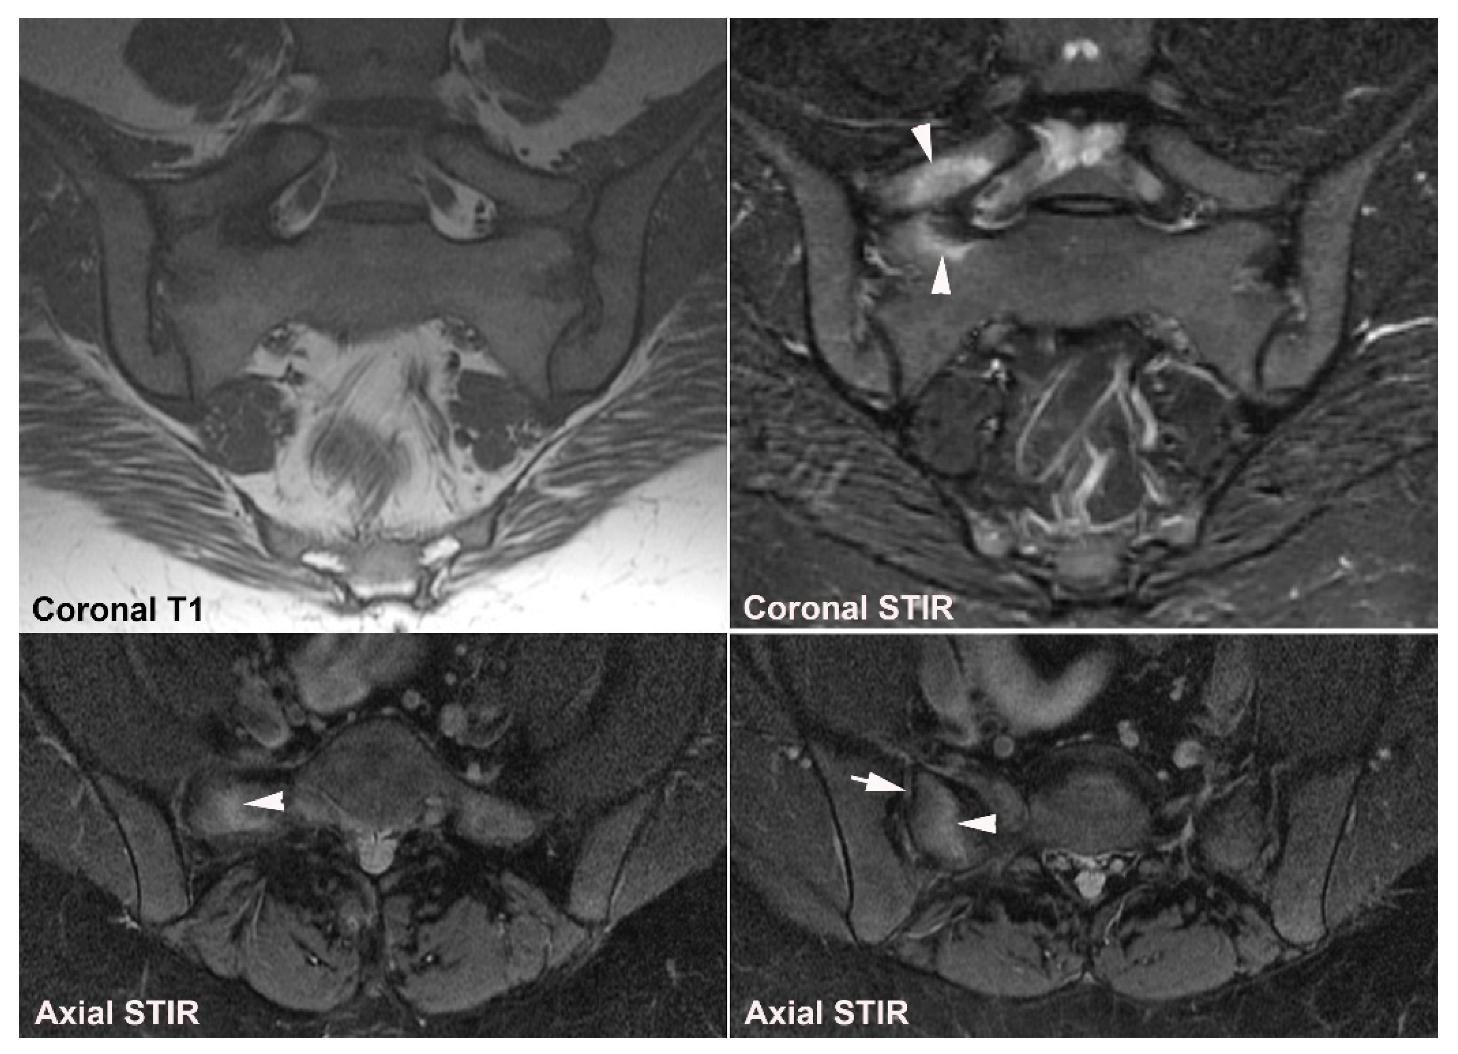

6. Other Strain-Related SIJ Changes

7. Degenerative SIJ Changes/Osteoarthritis